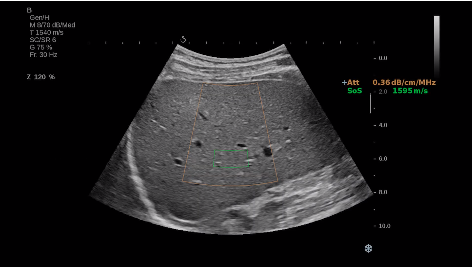

法國聲科影像(SuperSonic Imagine,SSI. Euroniex:FR0010526814)近日發(fā)表公告,宣布其研發(fā)的新一代“極速”超聲成像平臺(UltraFast Imaging),首次實現(xiàn)了肝臟的多項超聲定量評估新指標同步檢測,包括:Att PLUS,SSp PLUS和Vi PLUS等,基本涵蓋肝臟相關病理變化指征的如纖維化、脂肪變、炎癥等。據(jù)悉,此多項新技術新將搭載于新Aixplorer系列E超系統(tǒng)。

E超相關技術已被多項多中心大樣本研究證實對于肝纖維化無創(chuàng)評估有重要意義,同時也可全面應用于乳腺、甲狀腺、肝臟、前列腺、肌骨、婦科等全身各組織器官的定量評估和鑒別診斷。在慢性肝臟方面,聲科E超的肝臟相關定量診斷技術集,于2018年獲得美國FDA認證,成為FDA歷史上首次獲批的單病種超聲全面定量解決方案。

E超是在原有B超、彩超(彩色多普勒CDFI)基礎上研發(fā)成功的新一代超聲剪切波彈性成像系統(tǒng),是一種能夠全面應用于表淺組織、腹部臟器,血管等方面的組織彈性成像技術。根據(jù)組織硬度彈性值的不同,有效鑒別實性腫瘤的良惡性。對于惡性病變的診斷具有較高的特異性和敏感性,尤其對于甲狀腺、乳腺、前列腺等小器官,能夠完成常規(guī)超聲不能完成的組織定量分析,可以實時、全幅、全定量獲得組織彈性(硬度)信息,為鑒別腫瘤的良惡性提供客觀、量化的診斷依據(jù)。